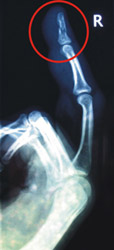

....not like this webmaster, who had a stupid accident and broken his finger on the right hand. No chance for bass playing these days! CU later,